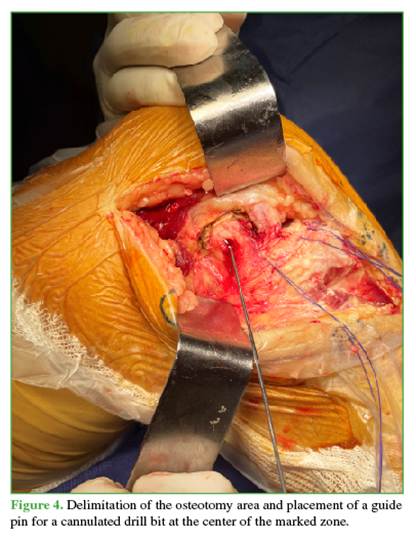

Including the popliteus insertion also increases the visualization area.2 A 3.5-mm cannulated drill bit is used to create a hole at 30° proximally and 30° anteriorly in the center of the marked rectangle, preparing the bone block for later reinsertion (Figure 4).